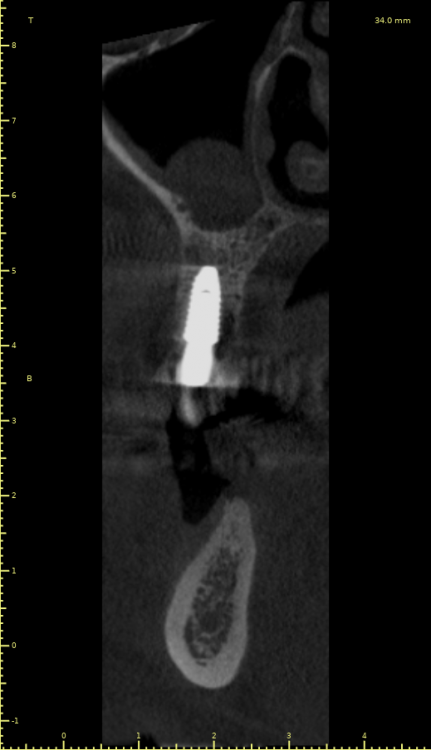

Женька Опубликовано 21 июля, 2021 Автор Поделиться Опубликовано 21 июля, 2021 3 месяца минуло... клык на торке 30 неприятные ощущения второй премоляр на 10 и подвижность... отправил на кт. Всё насмарку... Ссылка на комментарий

Борис80 Опубликовано 21 июля, 2021 Поделиться Опубликовано 21 июля, 2021 премоляр в любом случае недозаглубитом болеет... Ссылка на комментарий

Карен Аванесов Опубликовано 21 июля, 2021 Поделиться Опубликовано 21 июля, 2021 2 часа назад, Женька сказал: 3 месяца минуло... клык на торке 30 неприятные ощущения второй премоляр на 10 и подвижность... отправил на кт. Всё насмарку... Спишем на профессиональные вредности пациента курение и двухсот граммовые жимы на грудь , при переустановке, будет и легче и лучше. Гарантии какие были? Ссылка на комментарий

Irouil Опубликовано 21 июля, 2021 Поделиться Опубликовано 21 июля, 2021 1 час назад, Борис80 сказал: премоляр в любом случае недозаглубитом болеет... На момент установки не болел 3 часа назад, Женька сказал: Всё насмарку... Сочувствую Ссылка на комментарий